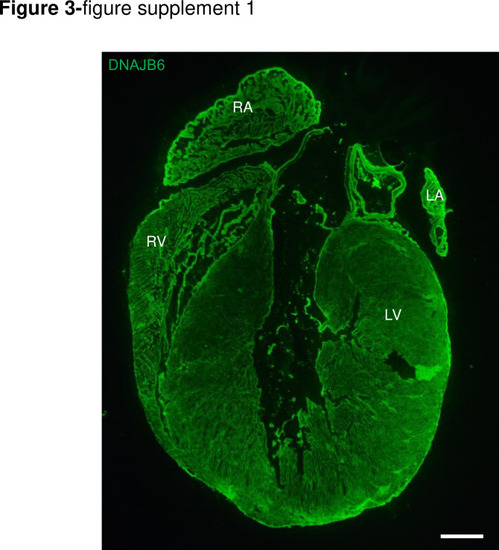

DNAJB6 is ubiquitously expressed in 4 cardiac chambers in mouse.Shown are immunostaining of a whole mice heart section using an anti-DNAJB6 antibody. Scale bar: 50 μm. RA, rigt atrium. RV, right ventricle. LA, left atrium. LV, left ventricle. |